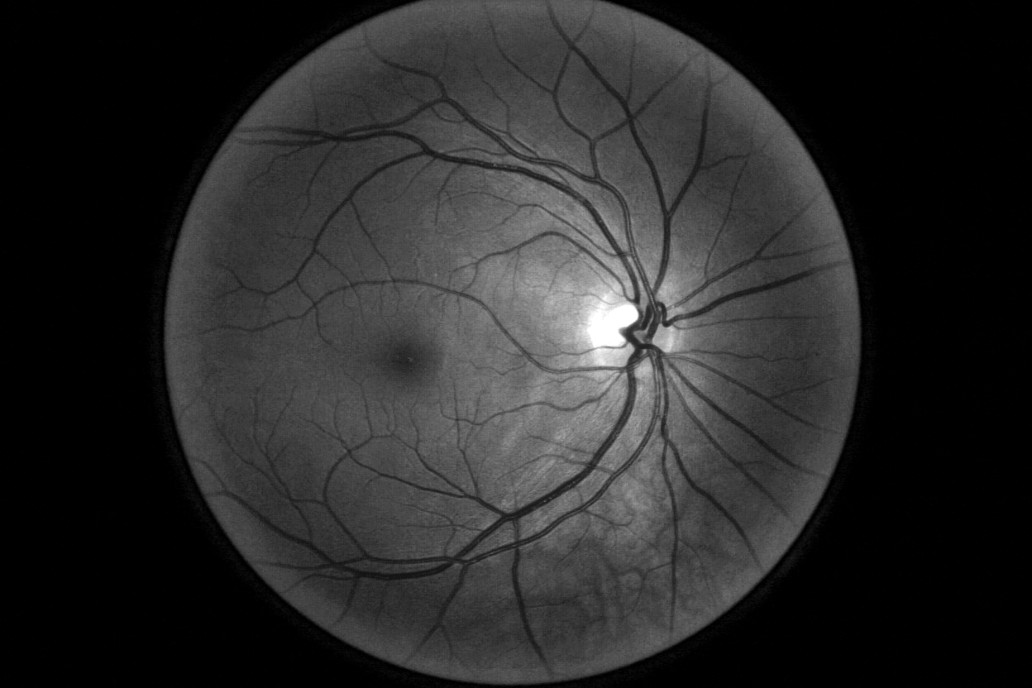

In the system Thailand had been using, nurses take photos of patients’ eyes during check-ups and send them off to be looked at by a specialist elsewhere – a process that can take up to 10 weeks. The AI developed by Google Health can identify signs of diabetic retinopathy from an eye scan with more than 90% accuracy – which the team calls “human specialist level” – and, in principle, give a result in less than 10 minutes. The system analyzes images for telltale indicators of the condition, such as blocked or leaking blood vessels. Sounds impressive. But an accuracy assessment from a lab goes only so far. It says nothing of how the AI will perform in the chaos of a real-world environment, and this is what the Google Health team wanted to find out. Over several months they observed nurses conducting eye scans and interviewed them about their experiences using the new system. The feedback wasn’t entirely positive.